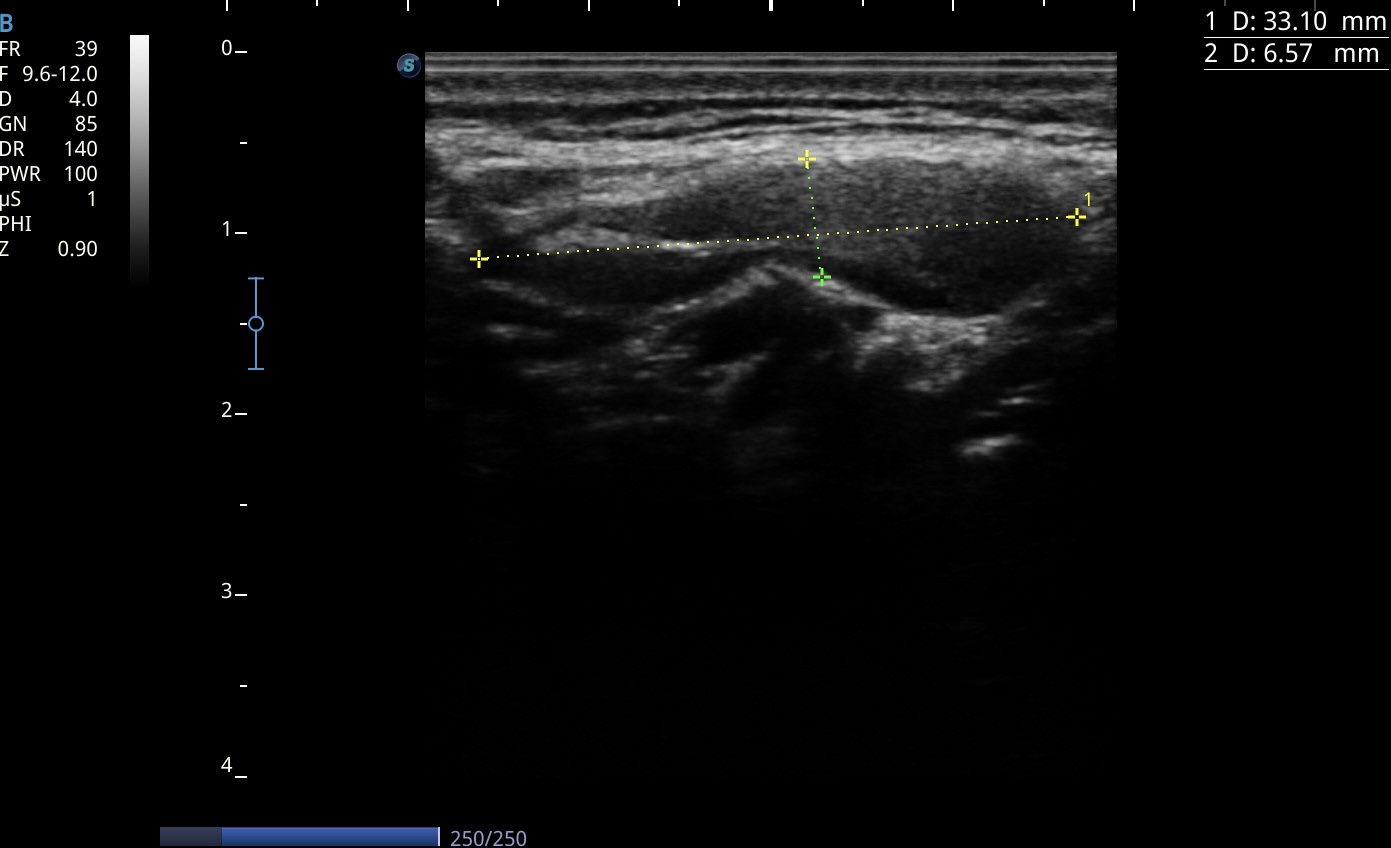

La experiencia consistió en incorporar un enfoque ecográfico metódico para la valoración de adenopatías palpadas en consulta. El protocolo se estructuró en la evaluación del eje corto, la relación eje largo/eje corto, la presencia y morfología del hilio ecogénico, la regularidad cortical, los contornos y el patrón vascular Doppler, pilares fundamentales para la estratificación ecográfica de adenopatías.

En todas las exploraciones realizadas se identificaron adenopatías benignas, mayoritariamente reactivas, en regiones cervicales, axilares e inguinales. Los hallazgos mostraron consistentemente morfología ovalada, hilio conservado, ecoestructura homogénea, cortical fina y vascularización central, características clásicas de benignidad.

La ecografía sistemática permite caracterizar adenopatías periféricas con precisión y aporta criterios sólidos para distinguir patrones benignos de posibles hallazgos sospechosos, aumentando la seguridad diagnóstica en Atención Primaria.